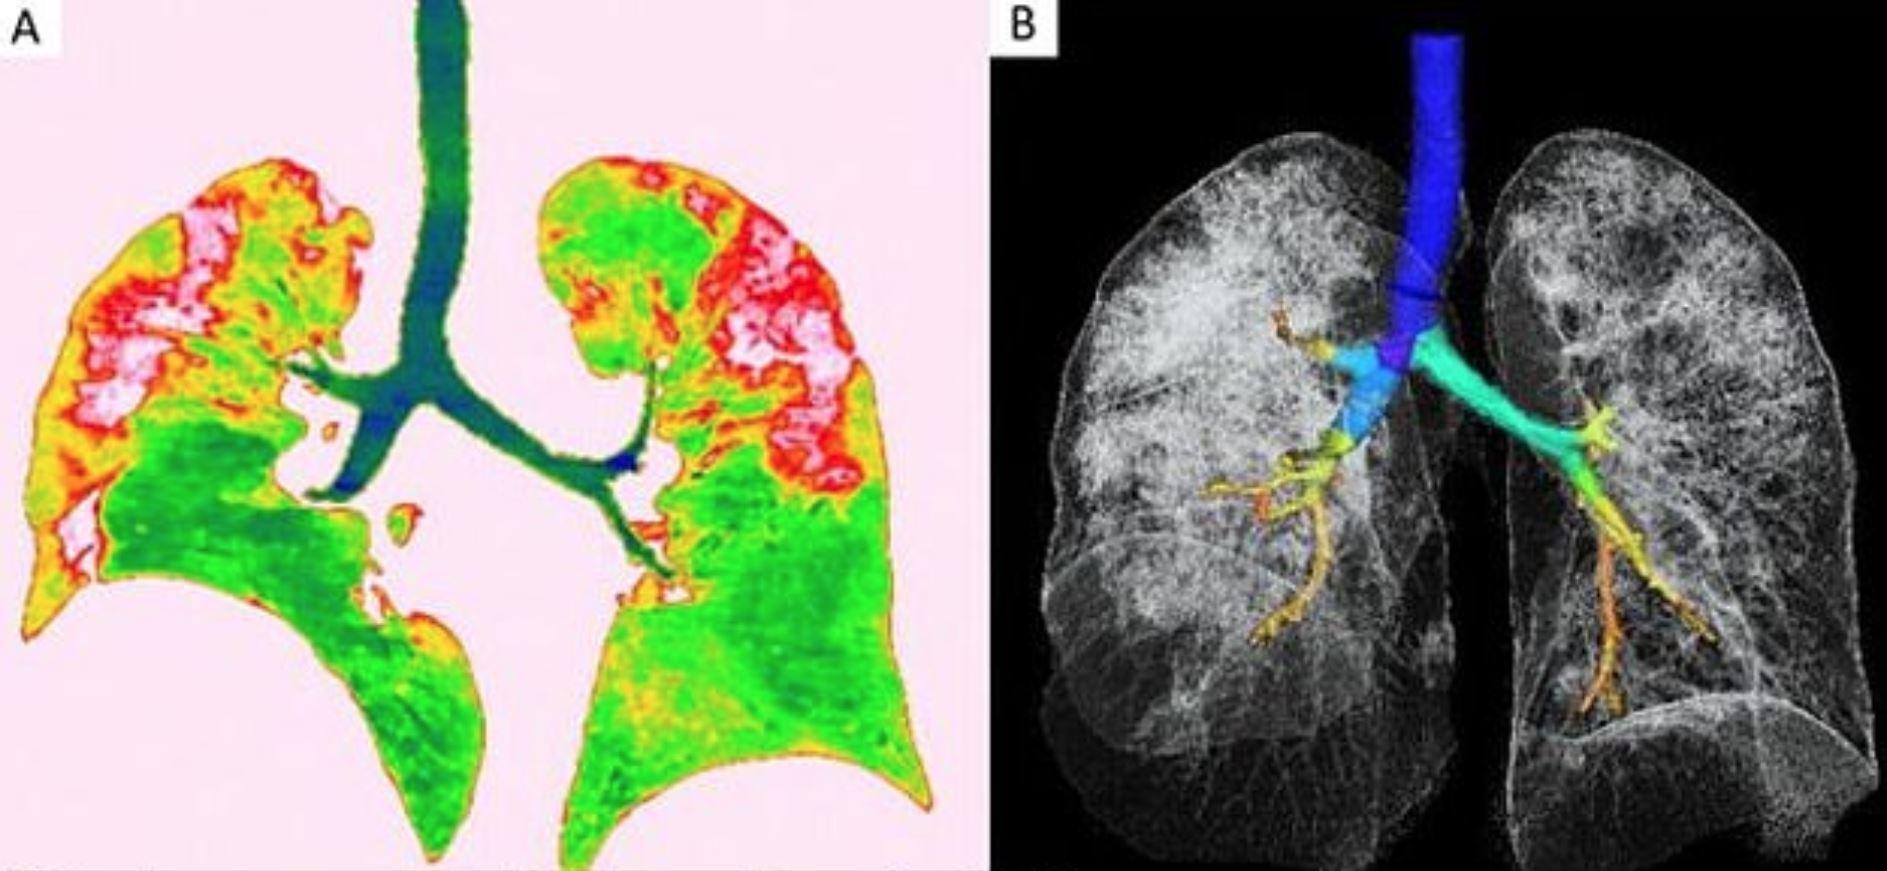

Ковид ассоциированный

Ковид ассоциированный 114 фотографий